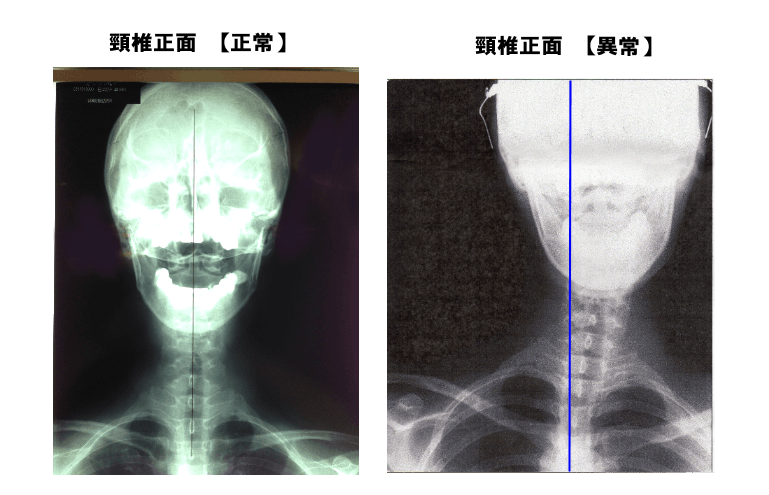

このテクニックの特徴は、不調の原因を「骨配列のズレ」に見い出し、レントゲン写真で骨格の異常を視覚的に確認してから施術を行うという点にあります。

「骨盤矯正」や「骨格矯正」とうたう整体院や治療院は数多くありますが、実際に骨の状態を目視せずに施術を行っているところがほとんどです。

どの骨が、どの方向に、どれだけ歪んでいるか―― それを触診や経験、あるいは“勘”に頼って矯正するのは、治療行為以前に“危険行為”だと私は考えます。

施術者だけでなく、お客様ご自身もレントゲン写真を通じて身体の歪みや姿勢の崩れを「見て理解する」ことで、納得のいく安全な治療が受けられるはずなのに、それが業界全体で行われていません。